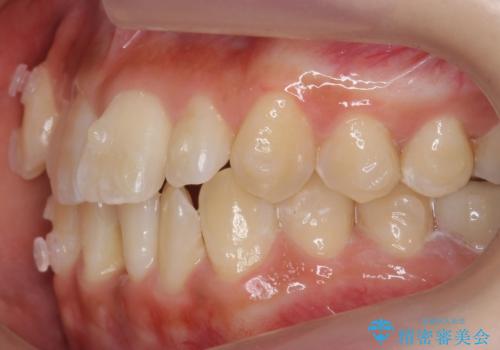

八重歯をインビザラインで 抜歯矯正

- 八重歯を主訴に来院。

出来るだけワイヤー矯正を避け、抜歯も最小限の本数をご希望でした。

下の前歯のみ1本抜歯しています。

下の前歯の周りの骨は薄いことが多く、無理に並べると唇側の骨がやせて歯ぐきが下がり歯が長く見えます。

それを回避するために今回は下顎前歯を一本抜歯をしています。